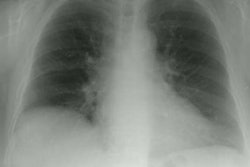

OBJECTIVE: The purpose of this study was to determine the patterns of non-CNS thromboses in patients with a hypercoagulable state associated with antiphospholipid antibodies (APA). MATERIALS AND METHODS: A search of our institution's clinical coagulation and immunology laboratories' records of patients examined from January 1993 to January 1996 revealed 1290 patients with APA. Computerized records of radiologic studies were reviewed for evidence of thrombotic events, which were found in 93 patients (49 males and 44 females; average age, 40 years). The anatomic distribution of thrombotic events was recorded. RESULTS: Fifty-five patients (59%; 29 males and 26 females; average age, 44.2 years) had solely venous thromboses, 26 patients (28%; 15 males and 11 females; average age, 33.1 years) had solely arterial thromboses, and 12 (13%; 5 males and 7 females; average age, 35.4 years) had both types of events. Deep vein thrombosis (DVT) of the legs was the most common finding, occurring in 45 patients (48%). Six patients had recurrent DVT. Other sites of venous thrombotic events included pulmonary embolism, 30 patients (32%); thoracic veins (superior vena cava, subclavian vein, or jugular vein), 10 patients (11%); and abdominal or pelvic veins, 18 events in 11 patients (12%). Sites of arterial thromboses included arteries supplying the upper limbs (great vessels arising from the aorta or the brachial, radial, ulnar, or digital arteries), 15 events in 12 patients (13%); aorta, one patient (1%); abdominal or pelvic arteries, 11 events in eight patients (9%); and arteries supplying the lower limbs (femoral or popliteal arteries), seven patients (8%). CONCLUSION: Venous thromboses were more common than arterial thromboses in our patient group, with DVT being the most common. However, thromboses in sites that are unusual for the general population were also relatively common. APA should be suspected in patients with thromboses in unusual sites or recurrent thromboses of an otherwise unexplained cause.